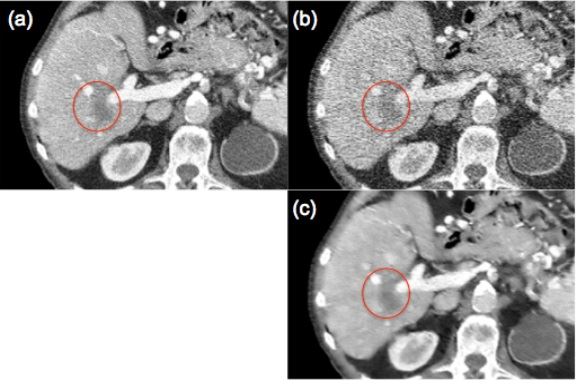

▲정상 선량으로 촬영한 CT 영상(a), 저선량으로 촬영한 CT 영상(b), 딥러닝을 이용한 영상결과(c). 붉은 원은 종양 부분이다.[사진제공=미래부] <br />

[아시아경제 정종오 기자] 컴퓨터단층촬영(CT)을 할 때 나오는 방사선 위험성을 인공지능과 첨단 IT 기술로 해결하는 방법이 나왔다. 예종철 카이스트 석좌교수 연구팀은 최신 인공지능 기술인 딥러닝 기술을 이용해 방사선량이 적은 저선량 CT 촬영으로도 임상에서 사용될 수 있는 고화질 의료영상 구현의 길을 열었다. X레이 CT는 대표적 의료 영상기술 중 하나로 선명한 3차원 영상을 제공한다. 여러 각도에서 반복적인 X선 촬영이 필요하기 때문에 다량의 방사선 피폭의 위험성을 지닌다. 병의 조기 진단이나 중재시술 등에 수반되는 반복적 방사선 피폭은 세포와 조직이 변형을 일으켜 암 등을 유발할 수 있다.이를 해결하기 위해 저선량 촬영을 시행하면 CT의 피폭 위험성을 낮출 수 있다. 영상 해상도가 크게 떨어질 뿐만 아니라 영상왜곡이 발생해 진단의 효용성이 떨어지는 단점이 있다. 기존의 영상신호처리 기술은 저선량 CT상에서 나타나는 복잡한 영상 복원문제를 해결하지 못했다. 저선량 CT는 영상진단 정확도가 떨어져 진단과 중재시술에 적용하는데 어려움이 있었다. 연구팀은 저선량으로 화질 저하 문제를 해결하기 위해 인공지능의 기술인 딥러닝 기술에 주목했다. 딥러닝은 심층 인공신경망 구조를 이용하는 알고리즘으로 최근 인공지능 분야를 주도하는 핵심 기술 중 하나이다. 기존에는 영상 분류와 관련된 분야에만 주로 이용됐다. 의료 방사선 피폭문제를 해결하기 위해 적용된 사례는 전무했다. 연구팀은 신호처리 기법인 웨이블렛(wavelet) 변환을 딥러닝과 접목시켜 새로운 알고리즘을 개발했다. 이를 통해 저선량 CT에서 발생하는 독특한 영상왜곡과 화질저하 문제를 성공적으로 해결했다. 예종철 교수는 "이번 연구는 최신 인공지능 기술을 접목해 방사선 피폭량을 획기적으로 줄일 수 있는 엑스레이 CT 원천기술을 개발한 것"이라며 "저선량 CT의 임상적용 등에 곧 상용화를 기대할 수 있어 그 동안 진단과 중재시술에서 문제가 돼 온 환자와 의료진의 방사선 피폭 문제를 근본적으로 해결하는데 기여할 수 있을 것"이라고 말했다. 정종오 기자 ikokid@asiae.co.kr<ⓒ세계를 보는 창 경제를 보는 눈, 아시아경제(www.asiae.co.kr) 무단전재 배포금지>